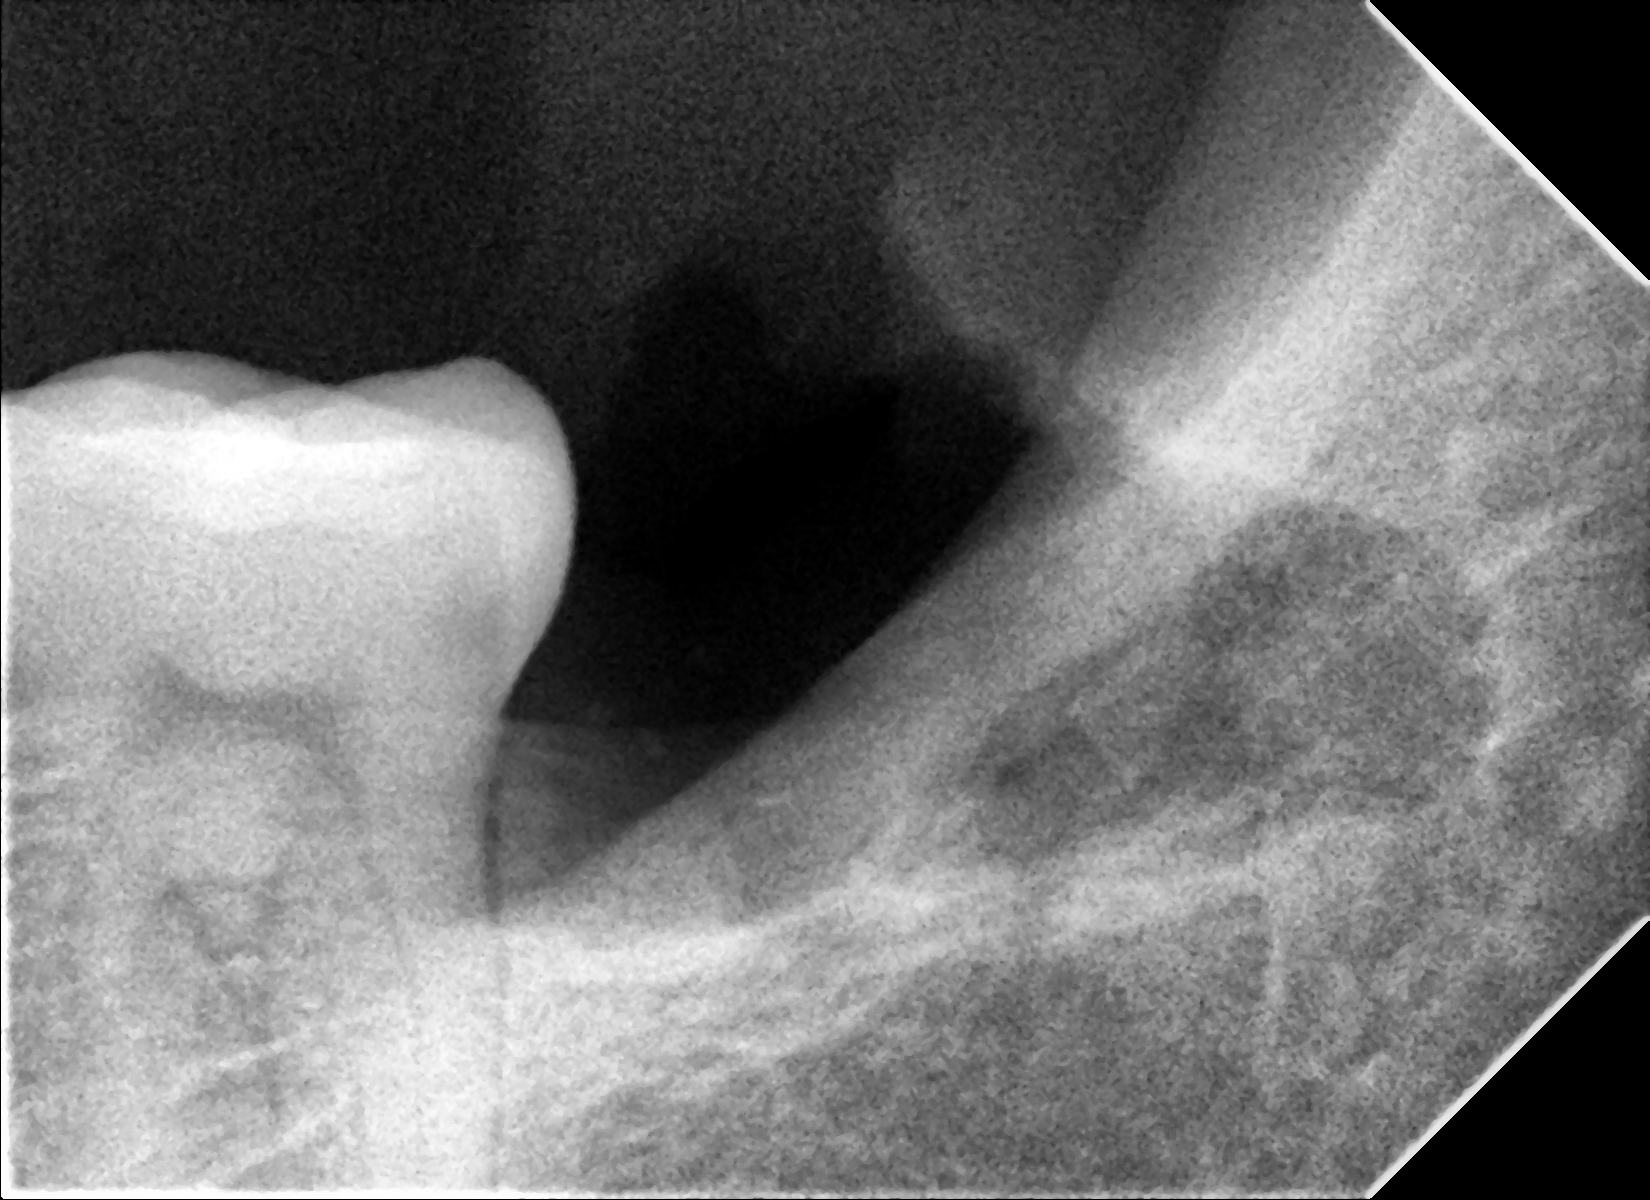

Paciente masculino 65 años, presenta Periodontitis Crónica Generalizada, se realiza extracciones totales de piezas superiores, se colocan 4 implantes dentales para sobredentadura, 4 meses después paciente disfruta de una nueva y renovada sonrisa, sin necesidad de retirársela, ni de preocupaciones de que la prótesis se le desplace al comer o hablar.